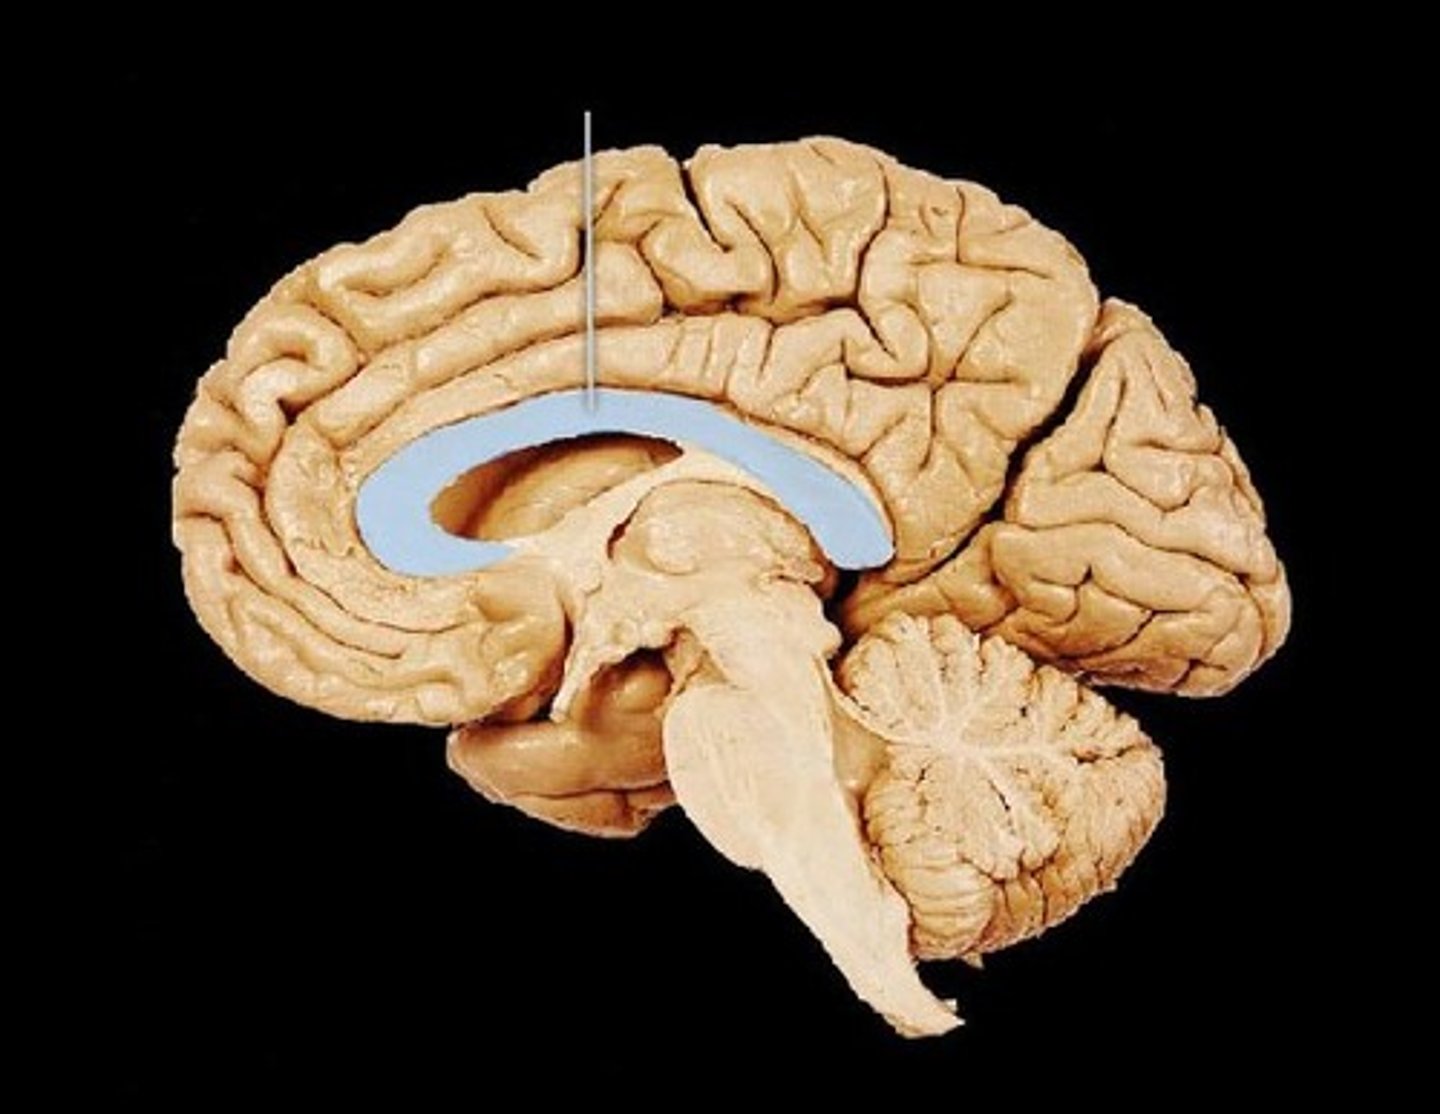

Corpus Callosum

Part of the limbic system. Band of nerve fibers which connect the 2 hemispheres of the brain. Ex: Allowing the left hemisphere to verbalize the name of an object seen in the right visual field.